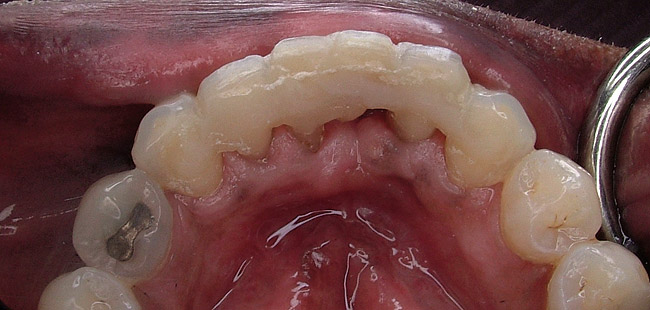

When fiber-reinforcing materials were introduced, the focus for their use was for periodontal splinting and stabilization resulting from tooth mobility.6,10,16,41-43 There is no doubt that splinting does reduce tooth mobility while the splint is in place.44 In the last decade, research supports the use of periodontal splinting as recommended therapy to stabilize those teeth to improve long-term prognosis.45-47 In a long-term clinical evaluation of splinting over a period of 48 to 96 months, using the original Ribbond Reinforcement Ribbon in fiber-reinforced composite resins was highly successful.17 The success of these splints can be attributed to close adaptation of the fiber ribbon to the tooth surface combined with cross stabilization of the mobile teeth by placing adhesive composite resin on the facial surfaces (Figure 4A, Figure 4B, Figure 4C, Figure 4D, Figure 4E).34,35 Splinting of traumatized teeth with fiber-reinforcing materials and adhesive composite resin has also been reported.48,49 When using fiber to stabilize the traumatized tooth or teeth or for tooth stabilization after re-implantation, the tooth must be allowed to have some movement and not be fixed in place.50,51